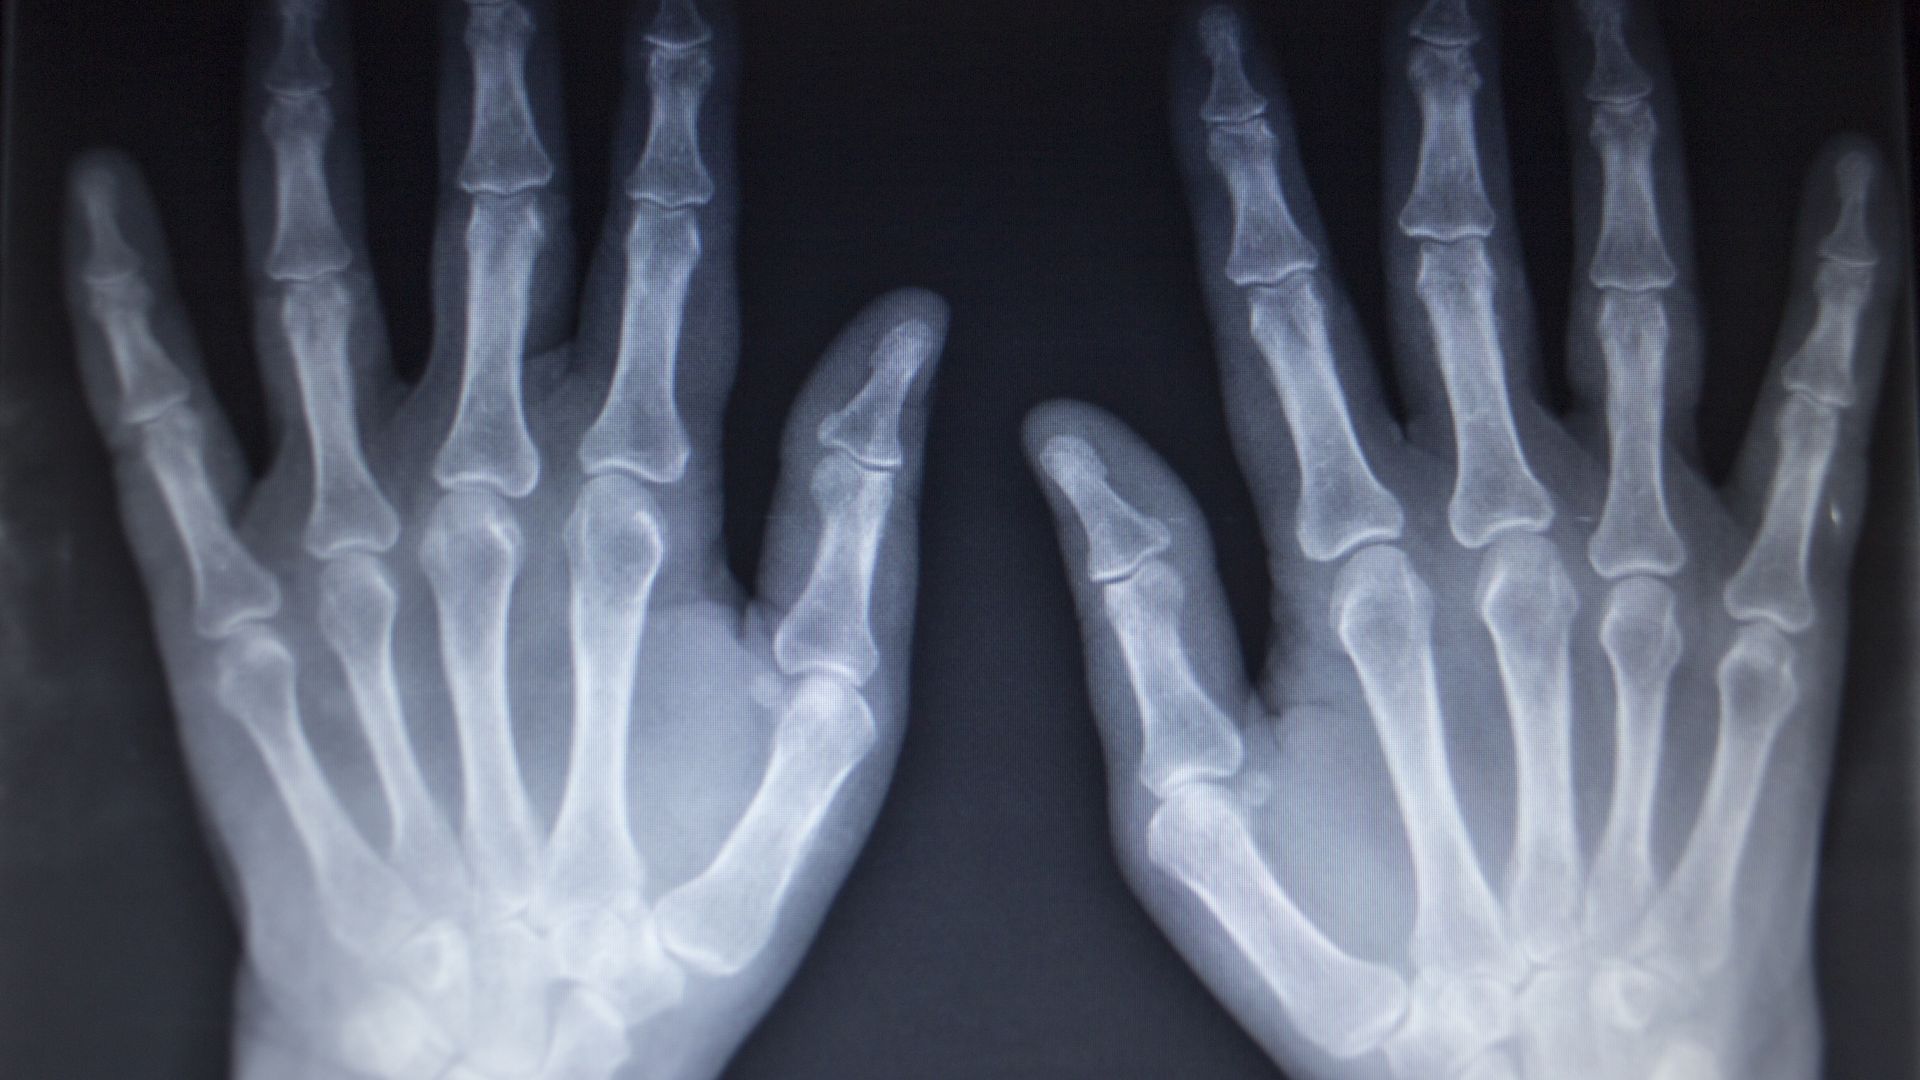

X-quang bàn tay là kỹ thuật chẩn đoán hình ảnh sử dụng tia X để tạo ra hình ảnh các xương và khớp của bàn tay, bao gồm xương cổ tay, xương bàn tay và các đốt ngón tay. Đây là phương pháp cơ bản, có giá trị cao trong đánh giá tổn thương xương bàn tay. X-quang bàn tay giúp bác sĩ quan sát rõ ràng hình dạng, vị trí, sự liên tục của các xương, từ đó hỗ trợ chẩn đoán chính xác nhiều vấn đề liên quan đến hệ xương khớp bàn tay.

Tia X đi xuyên qua bàn tay và bị hấp thụ khác nhau tùy theo mật độ của từng loại mô. Xương có mật độ cao sẽ hấp thụ tia X nhiều hơn và hiện rõ trên phim, trong khi mô mềm hấp thụ ít hơn và hiện mờ. Dựa vào sự khác biệt này, bác sĩ có thể quan sát hình dạng, vị trí, sự liên tục và mối liên hệ giữa các xương bàn tay một cách chi tiết. Nguyên lý này làm cho X-quang bàn tay trở thành công cụ hữu ích và được sử dụng rộng rãi trong chẩn đoán ban đầu.

Thông qua X-quang bàn tay, bác sĩ có thể phát hiện:

- Gãy xương bàn tay, xương ngón tay.

- Trật khớp hoặc bán trật khớp.

- Biến dạng xương sau chấn thương.

- Thoái hóa khớp bàn tay - ngón tay.

- Dị tật bẩm sinh của xương bàn tay.

- Một số dấu hiệu gợi ý bệnh lý viêm khớp mạn tính (như hẹp khe khớp, bào mòn xương).